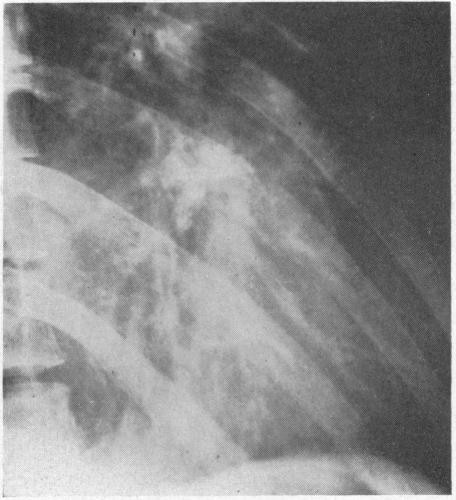

CARDIAC CALCIFICATIONS, ANNULAR AND VALVULAR (LEAFLET).

https://cdn.ncbi.nlm.nih.gov/pmc/blobs/8805/1643344/d27463516256/califmed00309-0004-a.jpg